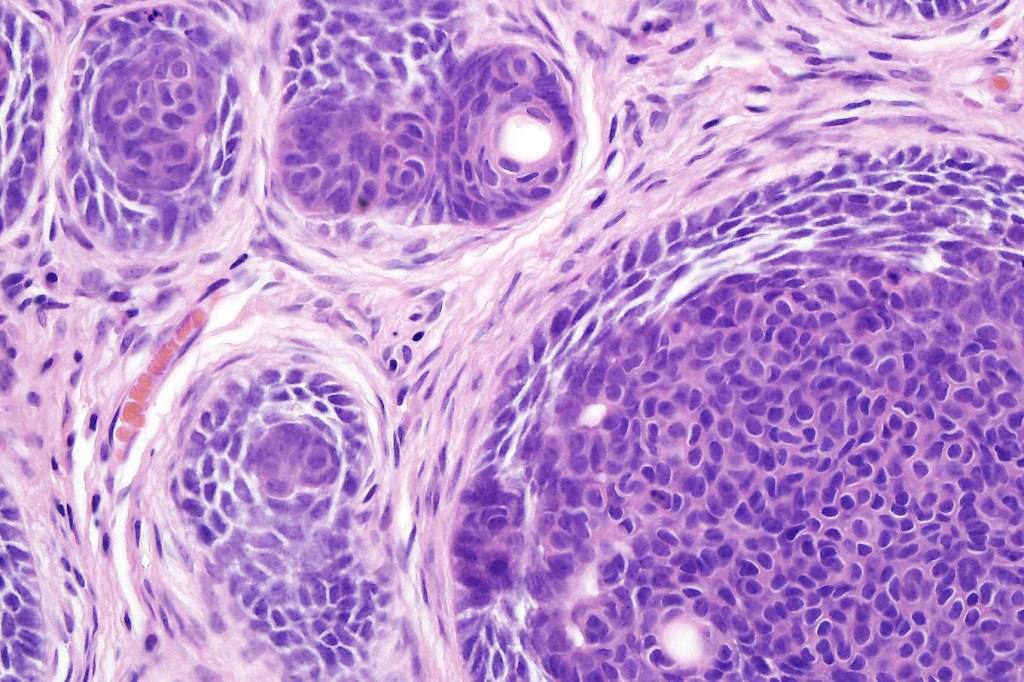

•Variably sized but generally large, basophilic tumor nodules composed of small uniform basaloid cells with minimal cytoplasm

•Peripheral palisading but no retraction artifact or stromal mucin deposition

•Variable keratocysts

•A rich fibromyxoid mesenchymal stroma with variable papillary mesenchymal bodies (sometimes these are absent)

•Trichogerminoma is a distinctive variant being composed of tumor nodules with basaloid cells surrounding pale or eosinophilic micronodules (Zellballen)